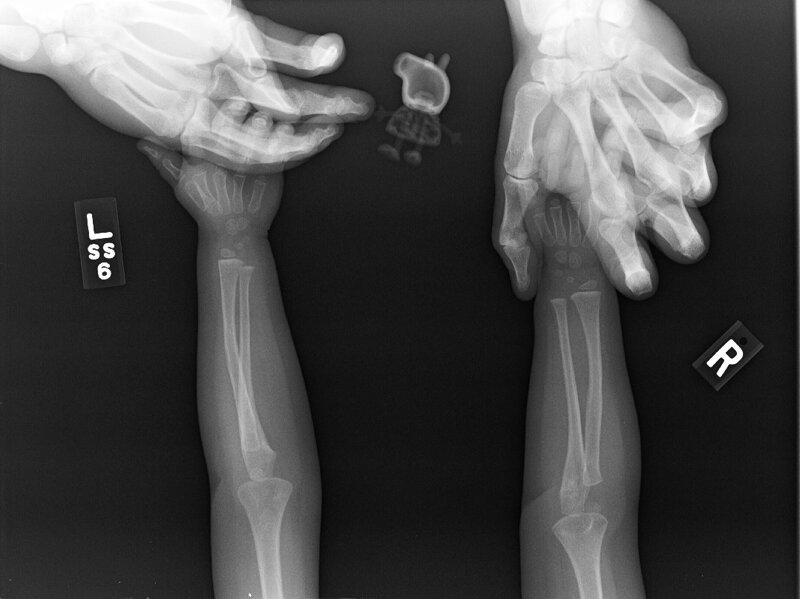

Дочь этой женщины отказывалась делать рентген без Свинки Пеппы